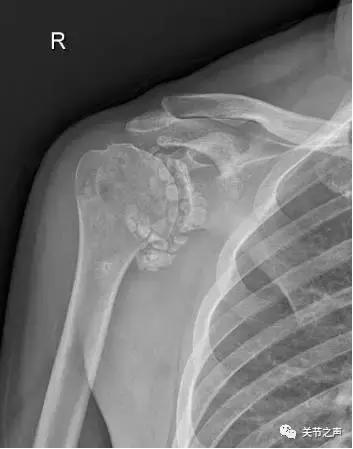

关节腔里的“珍珠”,就是我们常说的关节游离体,膝关节最多见,其次是肩关节。这种“珍珠”大多是一种良性肿瘤,叫滑膜软骨瘤病。

关节里长珍珠的症状:关节疼痛、卡压交锁例如:前不久,一位来自肇庆的许大姐因肩关节疼痛慕名来到暨南大学附属第一医院郑小飞主任门诊,X片显示他的肩关节长满了密密麻麻的“珍珠”。幸运的是,微创关节镜取“珍珠”是我们的看家本领,郑主任通过3个1cm的小切口就把他关节腔里的游离体全部取出,术后第二天开始康复功能锻炼。